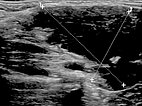

In der B-Bild-Sonographie (Querschnitt) zeigt sich die venöse Malformation ebenfalls kombiniert echoarm bis echofrei. Die echoreicheren Anteile entsprechen Abschnitten der VM, in denen das enthaltene Blut bereits geronnen ist. In den echofreien Anteilen ist das enthaltene Blut noch flüssig. Zudem findet sich ein kleiner Phlebolith in der Läsion, dies ist praktisch pathognomonisch für eine venöse Malformation.